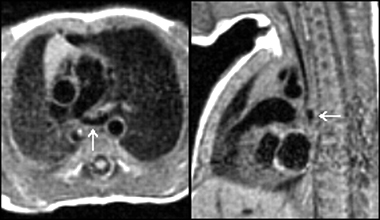

Envahissement tumoral de la paroi latérale du VG avec hypersignal T2 (séquence STIR) et hypersignal post-gadolinium (PSIR) chez un patient de 49 ans aux antécédents de séminome une quinzaine d’année auparavant avec récidive l’année précédente, traitée par chimiothérapie et extension sous forme de nodules pulmonaires et de métastase cérébrale traitée par radiothérapie. La paroi latérale infiltrée est hypokinétique avec FEVG abaissée à 54%.